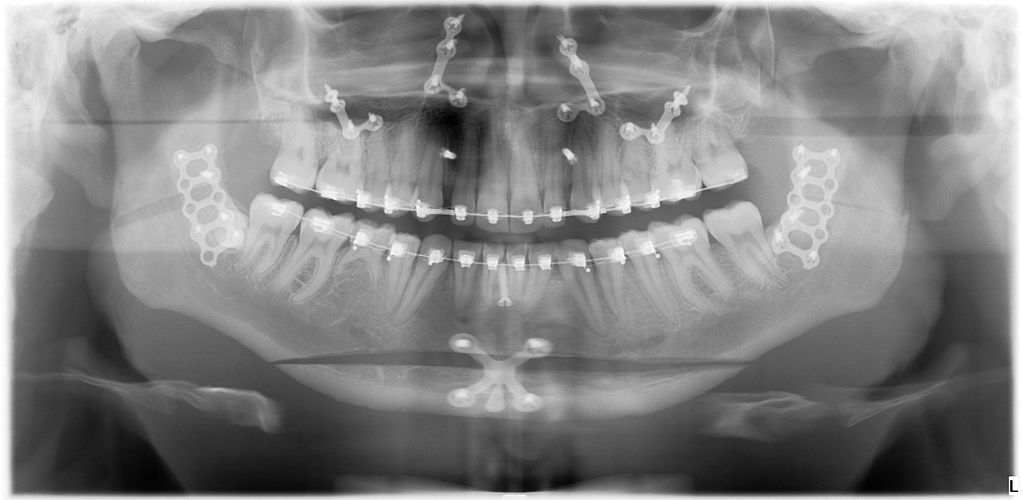

These are my CTs, how big do yall think i will ascend?

Before and after:

• Fabian_Noah_Luca_07022026_094045.png

Fabian_Noah_Luca_07022026_094045.png

2.4 MB · Views: 0